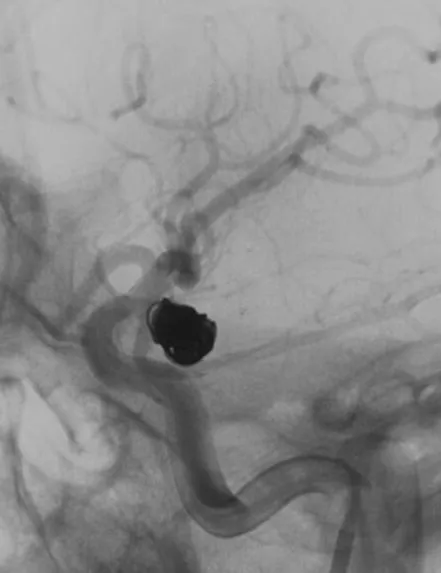

我们来看看动脉瘤的结构:红色为颈内动脉走向,绿色为后交通动脉走向,蓝色为动脉瘤

栓塞的要点,既要致密填塞,又要保证颈内动脉和后交通动脉的通畅。决定通过对侧前交通动脉-颈内动脉远端-后交通动脉途径来置入输送支架的微导管,从后交通动脉释放支架直到颈内动脉末端,以达到一个支架对颈内动脉和后交通动脉的保护

找到支架与弹簧圈之间的切线位,继续填塞。支架很好地保护住了颈内动脉和后交通动脉

最后的填塞结果